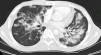

We report the case of 23-year-old man with human immunodeficiency virus (HIV) infection and a history of Kaposi sarcoma of the palate, treated with radiation therapy and antiretrovirals 2 years previously. He presented due to the appearance of violaceous skin lesions on the face, dyspnea and pleuritic pain with a CD4 T-lymphocyte count of 149cells/mm3 and viral load of 52092copies/ml. High resolution computed tomography of the chest (Fig. 1) revealed bilateral nodules with irregular margins and ground glass opacities, peribronchial cuffing and left pleural effusion. Bronchoscopy showed a raised lesion in the mucous membrane of the apical segment of the right upper lobe. Abundant hemosiderophages were found in the bronchoalveolar lavage (BAL) fluid, confirming alveolar hemorrhage. Immunohistochemistry was positive for human herpesvirus 8 (HHV-8). Treatment began with liposomal doxorubicin and antiretroviral treatment was switched. The patient remains alive at 8 months.

Chest computed tomography reveals poorly defined bilateral nodules, distributed symmetrically around the bronchial vessels (flame-like lesions). Other findings include septal peribronchial and interlobar cuffing, progressive air space consolidation and ground glass opacities.3